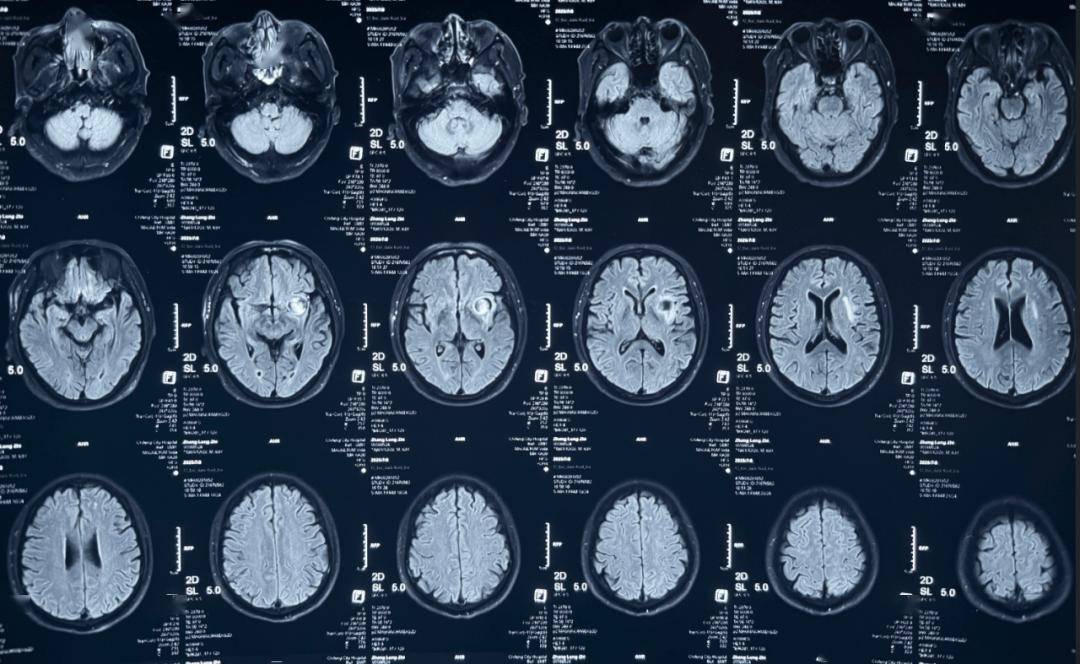

术后即刻造影

术后即刻造影,正侧位造影示载瘤动脉血流通畅,各主要分支血管显影良好,瘤腔内未见造影剂残余。

术后CT

术后即刻造影,正侧位造影示载瘤动脉血流通畅,各主要分支血管显影良好,动脉瘤仅余部分少量显影。